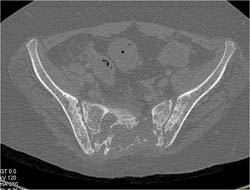

Metastatic Melanoma